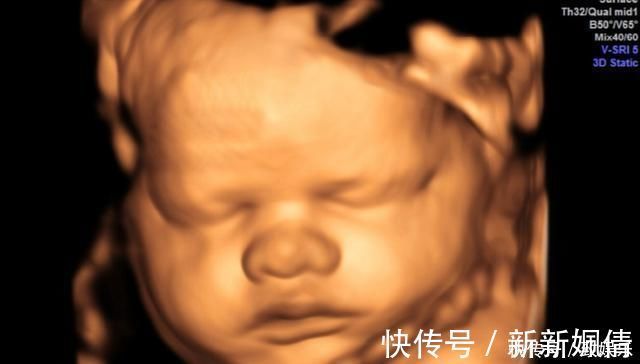

怀孕期间最重要的一项检查是大排畸检查,可以做三维彩超也可以做四维彩超。排畸检查都是绕不过去的检查,因为太重要了。

排畸检查可以查到胎儿的头面部、大脑、内脏器官、四肢、脊柱等外观是否正常,如果孩子有异常问题,需要孕妈妈们早做准备,别等到生下来再发现,到时候会给家庭带来精神和经济负担。